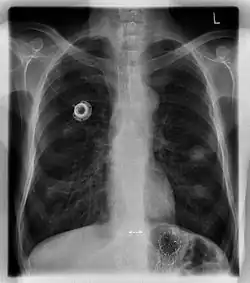

Chest X-ray showing an implanted port

A port is more correctly known as a "totally implantable venous access device". They are also commonly referred to as a Portacath or Chemo port. Brand names include Eco Port, Clip-a-Port, SmartPort, Microport, Bardport, PowerPort, Passport, Port-a-Cath, Infuse-a-Port, Medi-Port, and Bioflo.